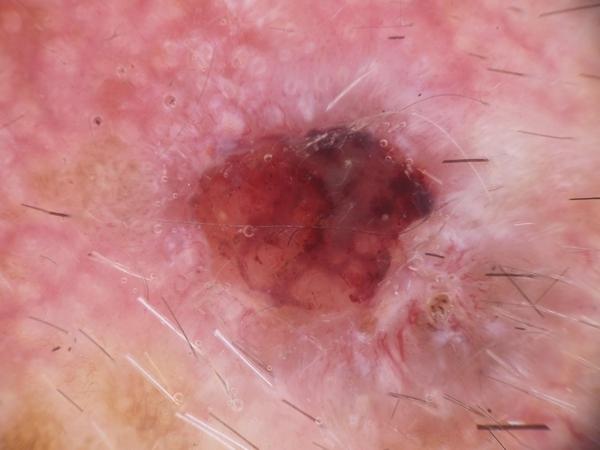

MILK10k consists of 10480 images, each representing a paired clinical close-up and dermatoscopic image for 5240 lesions. The dataset’s metadata include age (in 5-year intervals), sex, anatomic site, skin tone, diagnosis, method of ground truth establishment (histopathology or other means), and, if a dermatoscopic image of the same lesion was previously included in ISIC, its corresponding ISIC identifier. Skin tone is categorized into six levels, ranging from very dark (0) to very light (5), intentionally distinct from the Fitzpatrick skin types to avoid confusion. Most patients had skin tones in the middle ranges. Of the 5240 lesions, 95.7% were biopsied or excised, with histopathology serving as the gold standard for diagnosis. Diagnoses were mapped to both the ISIC-Dx diagnostic scheme and a simplified classification based on the ISIC2018/2019 challenge and HAM10000 diagnostic categories. The dataset includes 11 broad diagnostic categories: